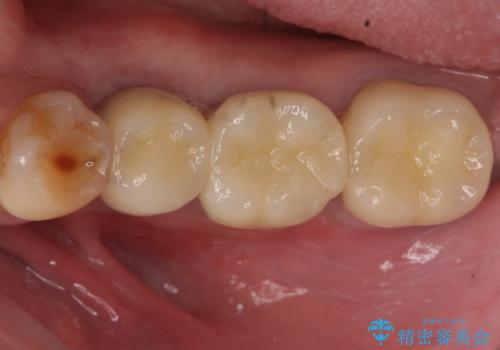

オールセラミッククラウンについて

今回用いたオールセラミッククラウンはジルコニアフレームという白い素材の上にセラミックを盛っているため、審美性が非常に高いのが特徴です。

また、ジルコニアは人工ダイヤモンドの材料にも使われているほど高い強度を持っており、そのためオールセラミッククラウンは審美性だけでなく、奥歯やブリッジの補綴も可能とするクラウンです。